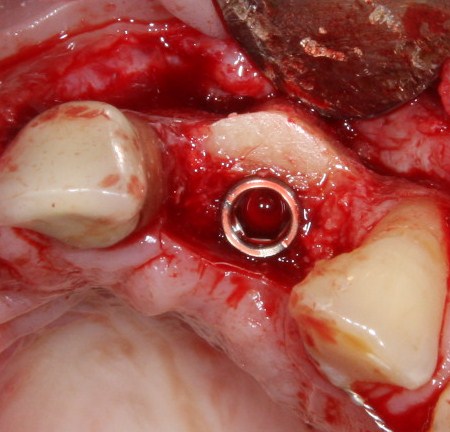

Убираем имплантодержатель. Обратите внимание, что полированная фаска вокруг шейки импланта находится над уровнем костной ткани. Чрезмерное погружение импланта — весьма распространенная имплантологическая ошибка.

Заглушка:

И швы:

Вот так она выглядит через день после операции:

Разумеется, пациентку никто не оставляет без зуба. Если Вы обратили внимание, то заметили справа на правой фотографии остатки металлического ретейнера. С помощью него к соседним от дефекта зубам фиксируется адгезивная коронка. Она, конечно же, не дает возможности нормально кусаться, но зато отлично маскирует отсутствие зуба. Таким своеобразным временным протезированием пациентка пользуется от начала и до конца лечения.